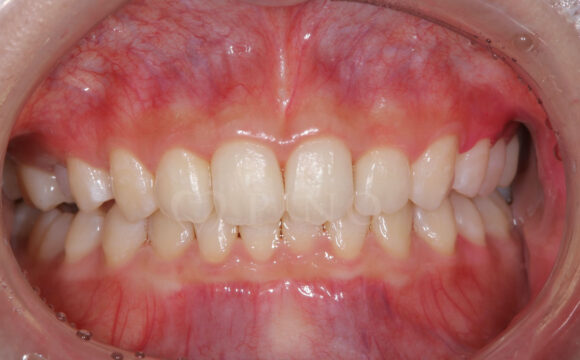

症例3:ワイヤー矯正後の後戻りが気になる(40代女性)

主訴 ワイヤー矯正後の後戻りが気になる 診断名 叢生 治療方法 マウスピース部分矯正 抜歯 なし オルソパルス なし 治療期間 9ヶ月 費用 436,000円 副作用・注意点 矯正後の後戻りを防ぐためリテーナーの使用が必要となる 備考 奥歯に噛み合わせ不良がない場合、部分矯正が適応となる -